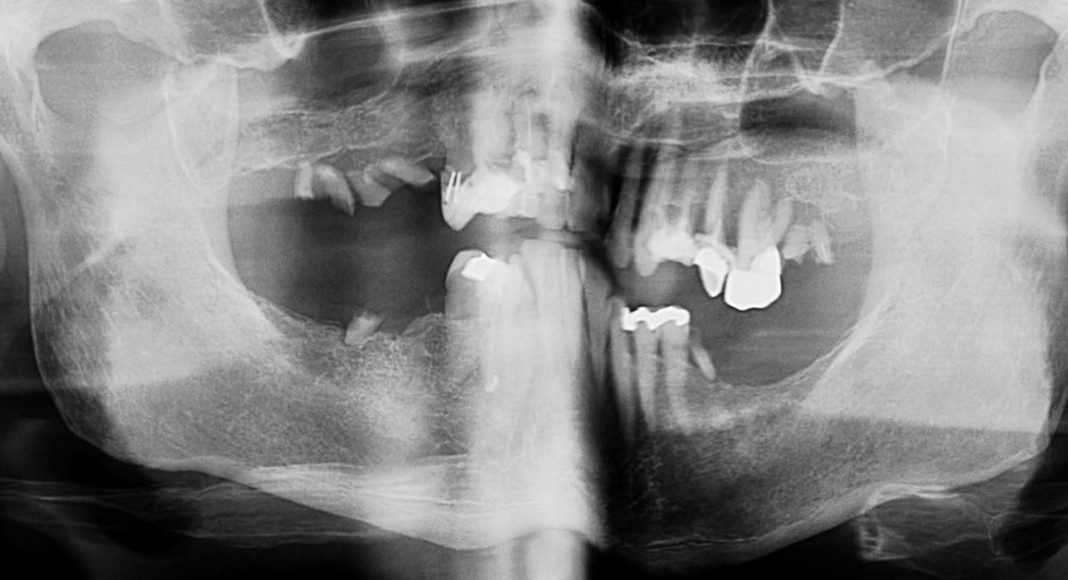

Day of surgery panoramic x-ray. Test implants were placed and adequate insertion torque was obtained (bone density and implant stability measured ≥ 25 Newton-centimeters) which qualifies multiple implants for immediate temporaries. All other teeth were extracted and a total of eight implants placed in the upper jaw (maxilla).